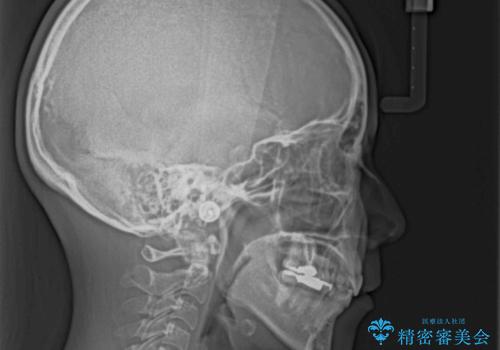

デコボコと口元の突出感 ハーフリンガルでの抜歯矯正

- 前歯のデコボコと上顎の前突感による口の閉じにくさを気にして来院された患者様です。

目立たない装置を希望されたので、上顎が裏側装置のハーフリンガルを選択し、上下左右の小臼歯(計4歯)を抜歯して矯正治療を行うこととしました。